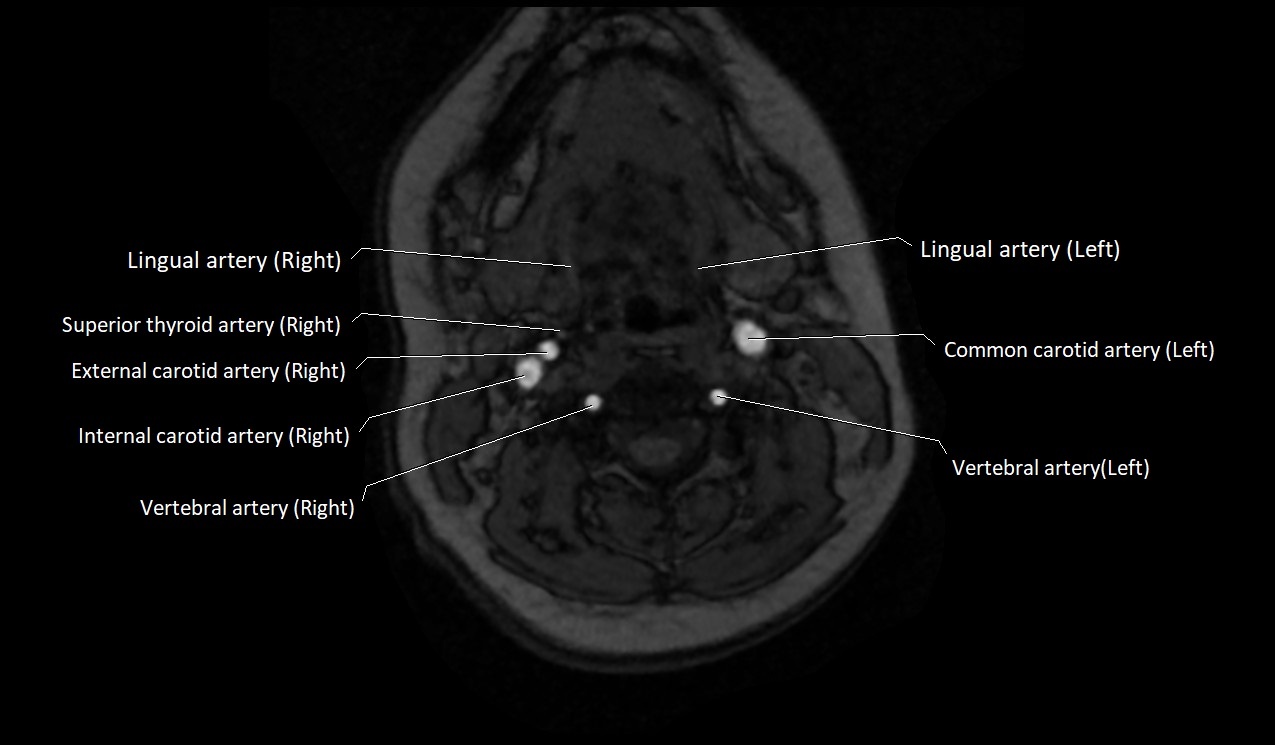

CT image

image